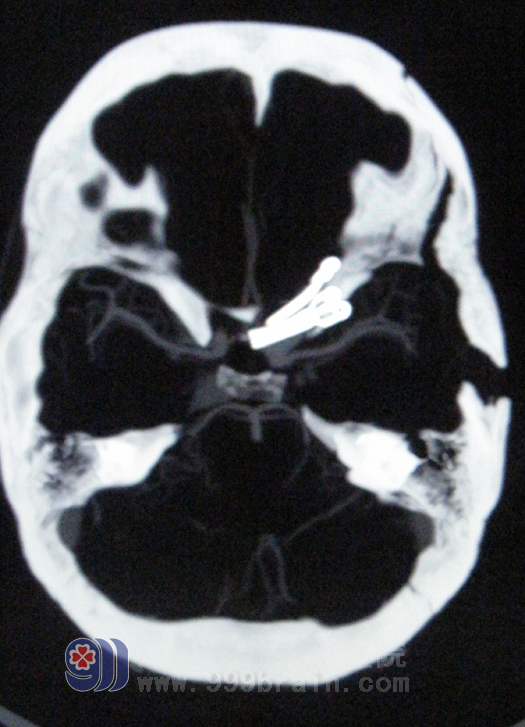

术后CTA

经过术前严格的方案制定及规范的Matas训练后,于8月1日为患者实施手术。术前先置入球囊,并行球囊阻塞耐受试验,术中暴露动脉瘤后充盈球囊闭塞颈内动脉近端,最后夹闭动脉瘤。手术过程非常顺利,术后患者所有生命体征都平稳。经过3周的休养,杨女士康复出院。该手术的成功,标志着我院动脉瘤手术水平已达到国内先进行列。 www.999brain.com